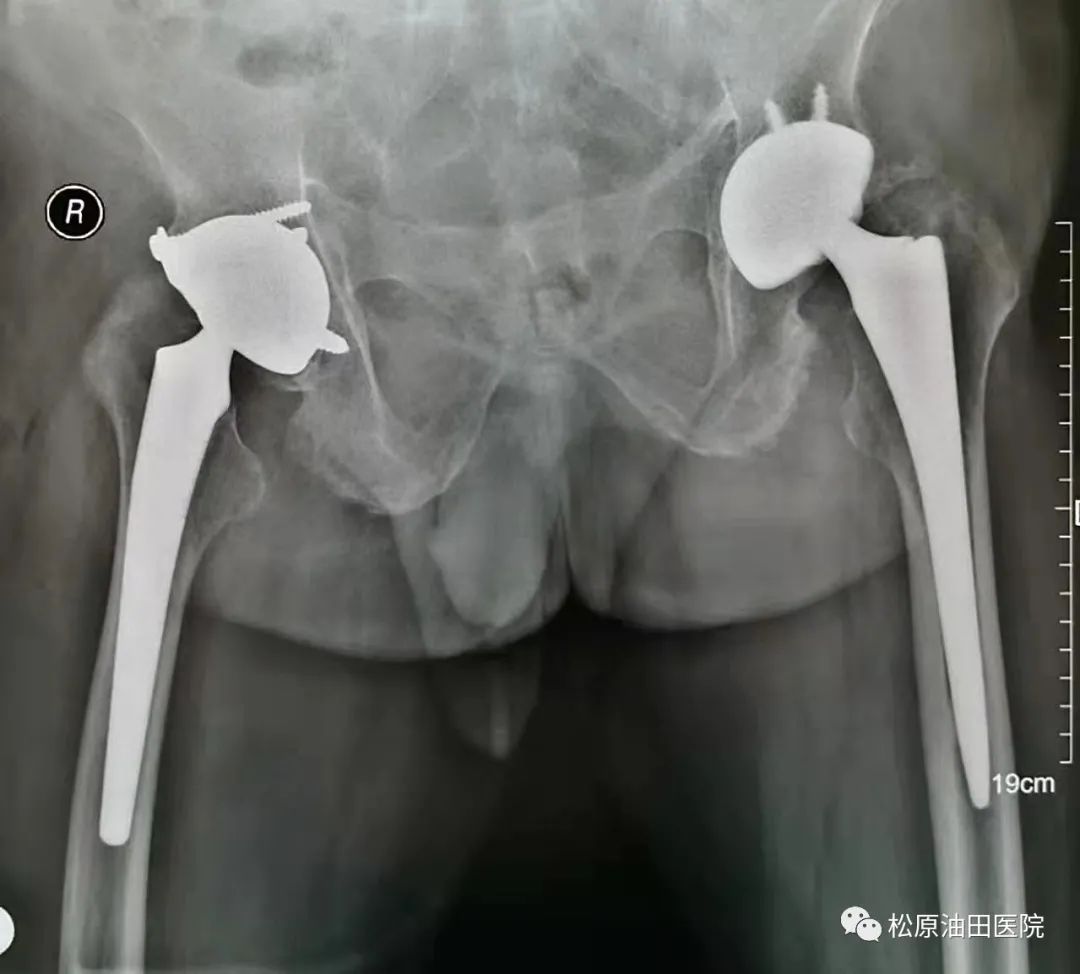

日前,松原吉林油田医院骨一科收治了一名55岁强直性脊柱炎右髋关节强直的男性患者。据了解,七年前他已行左侧髋关节置换,此次因右髋关节疼痛,活动受限而住院治疗。查体显示:右髋关节屈曲45度位强直,屈伸旋转及内收外展都不能。

面对着这“五大难”,骨一科还是迎难而上。他们结合影像学检查结果,经过全科人员认真分析讨论,决定为之实施人工全髋关节置换术,并针对可能出现的问题一一制定了相应的对策。手术由许德慧医生亲自主刀,在手术室、麻醉科的密切配合下,在科室人员共同努力下,他凭借深厚的理论基础和扎实的实践经验,手术历时1小时45分,终于顺利完成,术中很好的克服了所有的困难,没有留下任何遗憾。